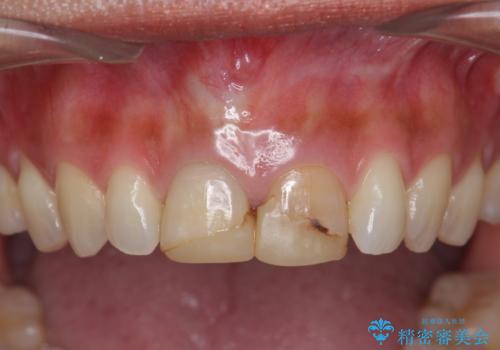

- 3週間後に迫った結婚式までになんとか前歯をきれいにしたいという希望で来院されました。

一回の治療時間を長く取り、限られた時間で最大限の結果を出せるよう集中治療を計画します。

- 32万円(仮歯・ファイバーコア・ジルコニアクラウンスペシャル×2)費用は治療当時の料金となります

ただ見えるクラウンを白くきれいにするのではなく、長期的な歯の予後を考えると根管治療・ファイバーコア築盛・精密な歯牙形成等クリアすべき条件は多々あると言えます。